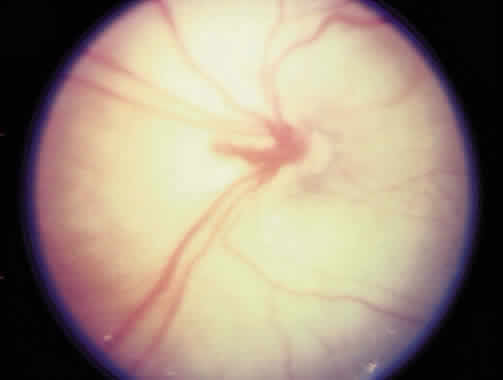

Laser is particularly useful in the management of zone I and posterior zone II disease. Most often, conjunctival incisions are necessary to get a cryotherapy probe posterior enough to treat zone I disease. This problem is obviated with laser delivery. Results of treatment of zone I disease in the Cryo-ROP Study are poor, whereas success rates of 80% to 90% have been reported in managing zone I disease with laser.71, 72, 73, 74, 75 Ridges in zone I or posterior zone II disease often are wider, with more defined vasculature than in zone II disease (Fig. 9). Zone I disease can be determined with a + 25 D lens. The disc is visualized at one rim of the lens, and avascular retina can be seen at the opposite rim when zone I disease is present (Fig. 10). A This occurs at a significant rate in the eyes of the smallest infants (500 g) with a gestation of 22 to 26 weeks. There may be an associated persistence of fetal vasculature (Fig. 11).

Fig. 9. Zone I retinopathy of prematurity with a flat ridge.

Fig. 10. Zone I retinopathy of prematurity determined with a + 25 D lens. The optic nerve is seen at the 9-o'clock position on the rim of the lens and avascular retina at the 1- to 5-o'clock positions on the rim of the lens.